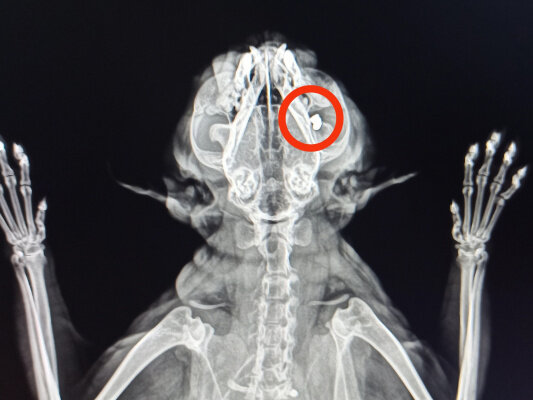

В Нижнем Новгороде зоозащитники спасают кота Тома, в которого стреляли неизвестные.

Животное попало к волонтерам год назад. Котику провели операцию, и достали из спины пулю. Казалось, мучения Тома позади, но спустя несколько месяцев коту становилось хуже – мучили проблемы с глазом. Прописанное лечение не помогало, и зоозащитники вновь обратились к ветеринарам.

Тогда в ходе обследований и выяснилось, что в нёбе кота застряла еще одна пуля. Том уже перенес очередную операцию. Сейчас он восстанавливается, и, как надеются медики и волонтеры, сможет жить нормальной жизнью.

Фото: котокафе "Мурзик"